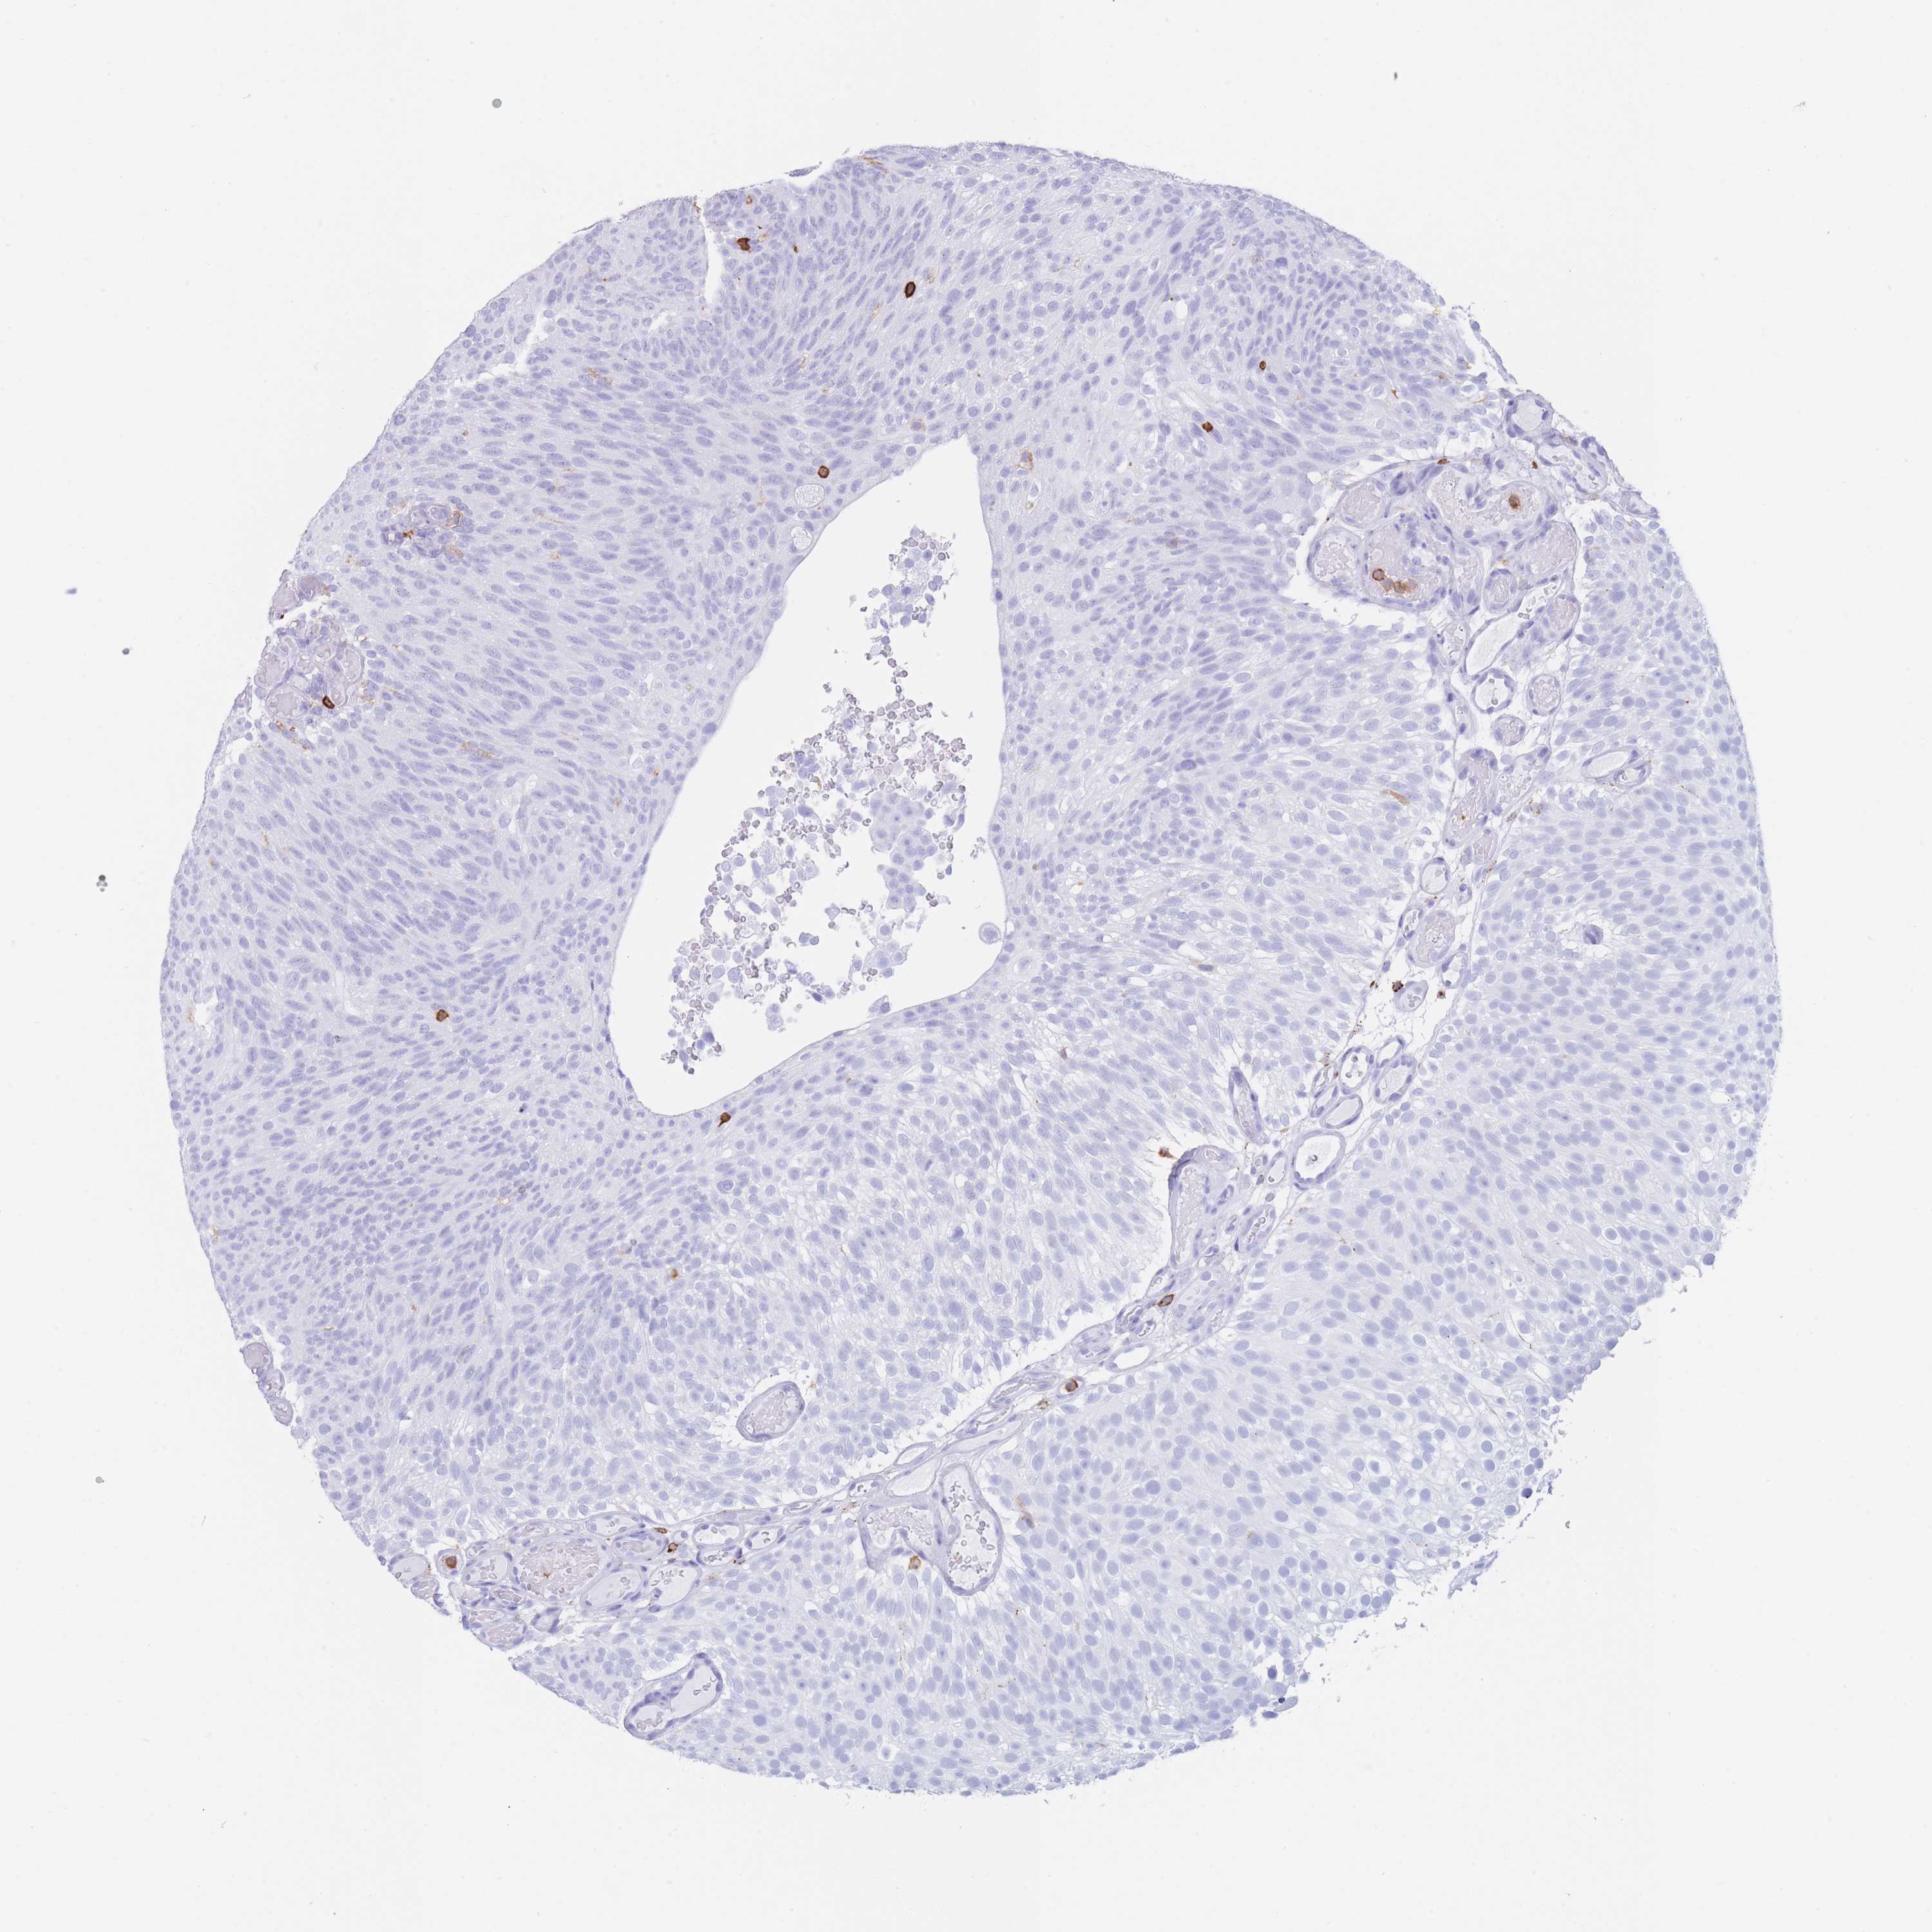

UROTHELIAL CANCER - Protein expressioni

A mouse-over function shows sample information and annotation data. Click on an image to view it in a full screen mode. Samples can be filtered based on level of antibody staining by selecting one or several of the following categories: high, medium, low and not detected. The assay and annotation is described here.

Antibody stainingi

Antibody staining in the annotated cell types in the current human tissue is reported as not detected, low, medium, or high, based on conventional immunohistochemistry profiling in selected tissues. This score is based on the combination of the staining intensity and fraction of stained cells.

Each image is clickable and will lead to virtual microscopy that enables deeper exploration of all samples and also displays staining intensity scores, fraction scores and subcellular localization as well as patient and tissue information for each sample.

Antibody HPA051132

Antibody CAB046473

Staining

High

Medium

Low

Not detected

Intensity

Strong

Moderate

Weak

Negative

Quantity

>75%

75%-25%

<25%

None

Location

Nuclear

Cytoplasmic/membranous

Cytoplasmic/membranous,nuclear

Urothelial carcinoma, High grade

Urothelial carcinoma, Low grade